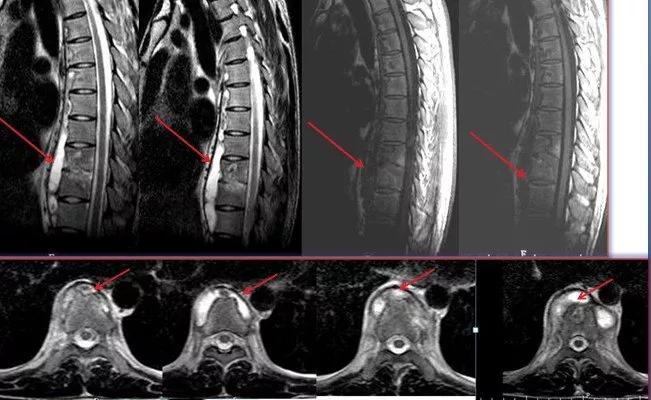

3、这是一个年轻男性患者,也是因轻微背痛就诊。影像检查发现胸椎结核。从核磁看(红色箭头示)胸椎多节段椎前广泛脓肿,只有两个椎体和椎间隙有明显炎性病变或破坏。

患者是年轻人,轻微背痛,活动甚至体育锻炼都不受影响,可以采取保守治疗。制定抗结核治疗方案后,定期随诊复查。抗结核治疗六个月后,脓肿没有吸收,还较以前增大(红色箭头示),但患者活动锻炼没有任何影响,椎体及间盘破坏也无加重。继续保守治疗,调整抗结核药物组合方案,并辅以中药治疗。

抗结核治疗九个月后,脓肿明显吸收(红色箭头示)。